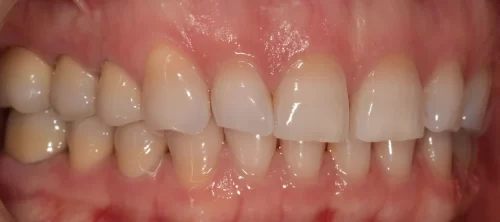

Tímea, kiterjedt amalgám tömések miatt elszíneződött fogait kerámia leplezésű cirkónium koronákkal láttuk el.

A metszőfogak közötti rést kompozit tömőanyaggal zártuk a páciens kérésére.

Az eredmény önmagáért beszél!